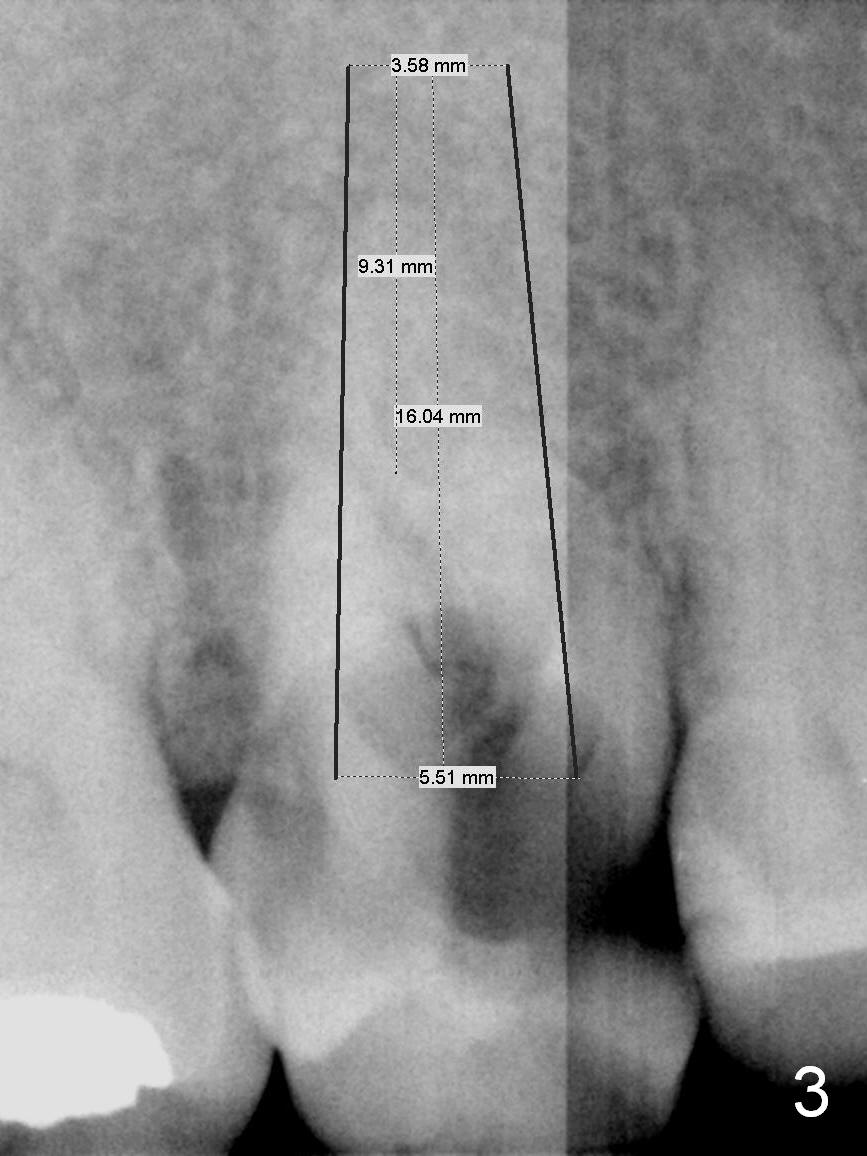

A 52-year-old woman is a dental phobic.  Her main concern is the tooth #3 with caries apparently involving the furca (Fig.1 ^).  Before extraction, take photos to show a polyp in the pulpal chamber, which is most likely periodontal.  After extraction (prepare surgical handpiece, since the tooth most likely fractures at extraction), take photos to show furcal perforation, while the socket is packed with 3 pieces of gauze soaked with Metronidazole.  There is apparently sufficient bone apical to the roots (Fig.2).  To achieve primary stability, use an implant as long as possible (13 mm of IBS, Fig.3 (implant is drawn to be placed too superficial)) with large diameter appropriate to the septum.  The plateau of the implant will be placed apical to the crests and coronal to the septum.